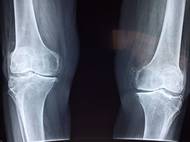

Šumperská nemocnice eviduje skokový nárůst artróz. Může za to pandemie covidu?

Nárůst počtu pacientů s artrózou kolenních kloubů a kyčlí evidují v posledních měsících lékaři Nemocnice Šumperk, kteří vyšší počet případů těchto degenerativních onemocnění kloubů…